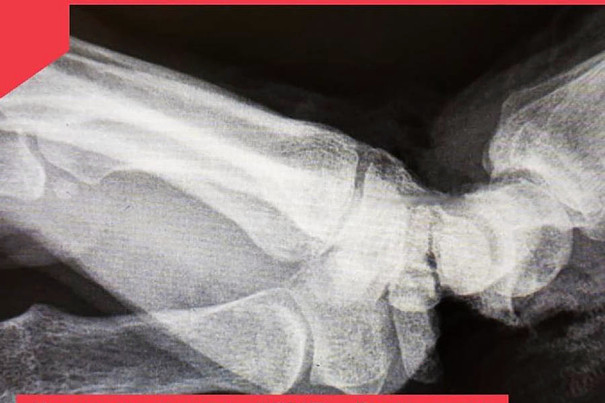

Сотруднице одного из владимирских предприятий ножом для резки пленки отсекло кисть в области соединения с предплечьем правой руки.

В результате несчастного случая кисть была практически оторвана и держалась только на маленьком кусочке кожи. Сосуды, нервы, сухожилия и основная часть мягких тканей были отрезаны.

На месте незамедлительно началась операция по восстановлению кисти. Операция прошла успешно, и женщина уже находится дома. Теперь ей предстоит длительное восстановление.